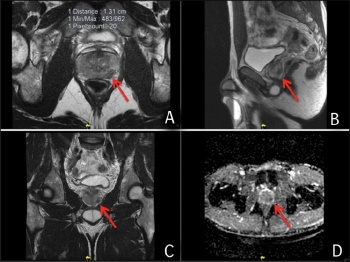

The image in Figure 2 demonstrates a large anterior prostate lesion with abnormalities on the diffusion weighted imaging, strongly suggestive of an underlying cancer. A targeted prostate biopsy of this anterior prostate cancer revealed Gleason 3+4 prostate cancer involving 60% of two cores. Staging scans did not demonstrate any disease beyond the prostate and the patient underwent a nerve sparing radical prostatectomy. He made an excellent functional recovery and has remained free of biochemical recurrence.

Figure 2. MRI images demonstrate a lesion on the anterior surface of the prostate in image A, with diffusion abnormalities in image B